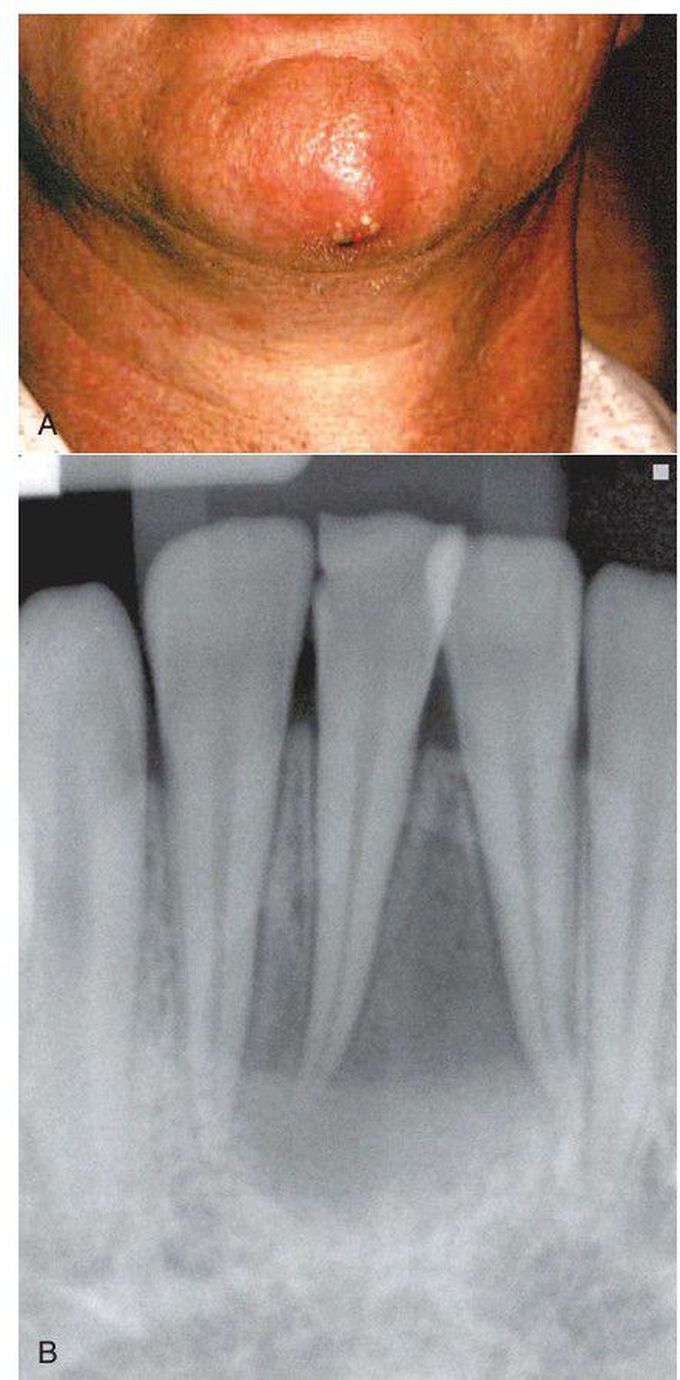

A, Extraoral sinus tract opening on the skin in the central chin area. B, Radiograph of mandibular incisors and canine after root canal therapy.